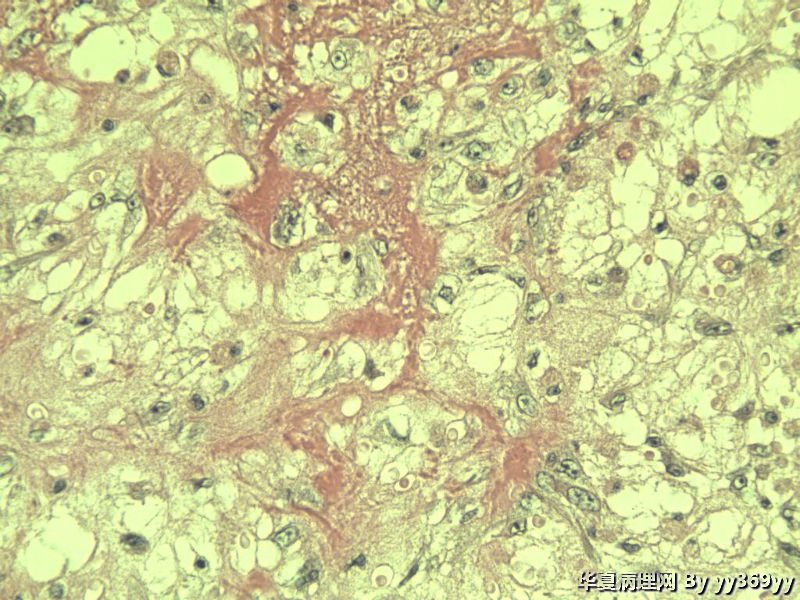

男 30岁 小肠一段,肠管严重粘连可见一体积为 2.5 × 2 × 1.5 cm3的肿块,切面灰白,实性,质中

小肠肿瘤图2

从最后这几张高倍镜图看,淋巴样细胞弥漫性增生,很可能是淋巴瘤。

恶性肿瘤   淋巴瘤 脂肪肉瘤  低分化腺癌 做IHC

考虑炎性肌纤维母细胞瘤、炎性纤维性息肉、胃肠间质瘤,不考虑淋巴瘤

考虑炎性肌纤维母细胞瘤

只是倒数那几张是取自淋巴结吗,还是所有的? 考虑恶性GIST,做IHC